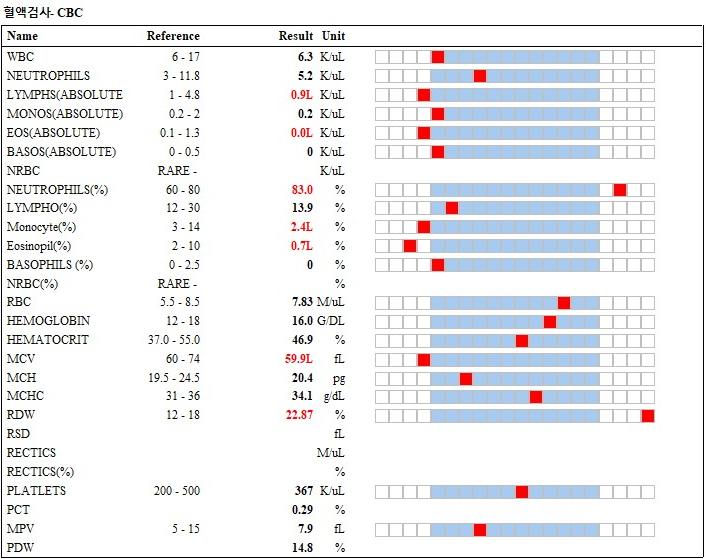

혈액검사에서 특이 소견은 관찰되지 않았습니다.